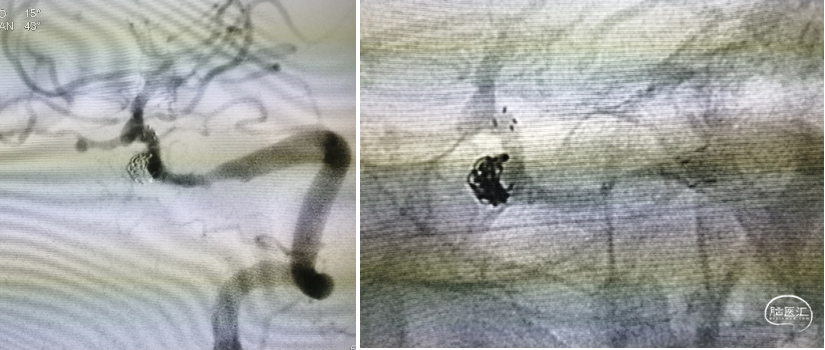

Gateway 2.0 mm×15 mm球囊命名压缓慢后扩支架

栓塞结束后造影情况,可见支架贴壁良好,血管狭窄较前改善,动脉瘤近全栓塞,远端大脑后动脉显影明显改善

术后DWI提示左侧小脑半球点状小梗死灶,患者无新增神经功能障碍,术后第三天出院